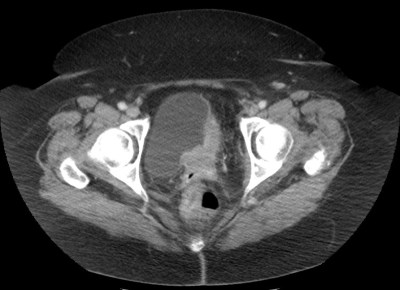

UROGRAFÍA – TCMD:

En series de estudio se ha estimado una sensibilidad, especificidad, VPP y VPN del 93%, 99%, 98% y 97% respectivamente. Se realiza añadiendo cortes finos, con una fase excretora, una buena hidratación del paciente y con el uso de diuréticos para conseguir una buena dilatación de la vejiga y una adecuada opacifiación de la misma.

Se debe jugar con las ventanas, usar amplias y estrechas , con el fin de maximizar la búsqueda de defectos de repleción. Se debería incluir el estudio de imágenes en axial y coronal, ya que algunas lesiones son más evidentes en una orientación que en otra.

Apariencia de las neoplasias de la vejiga:

- Masas focales y Defectos de repleción.

El engrosamiento difuso de la vejiga suele deberse a entidades benignas como la cistitis, obstucción o vejiga neurógena; muy raramente corresponden a cáncer.

Los tumores < 1 cm pueden pasar desapercibidos, por que el uso de una urografía TC no debe excluir la necesidad de realizar una cistoscopia en pacientes con hematuria y alto riesgo.